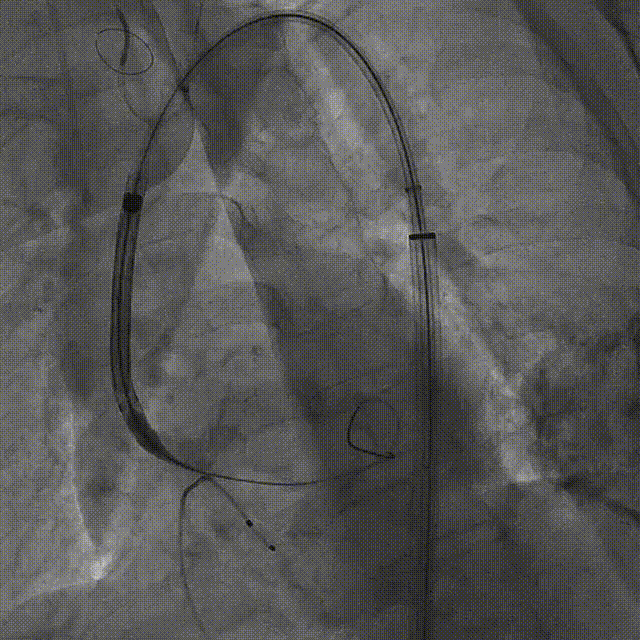

宋光远教授 首都医科大学附属北京安贞医院(点击查看专家详细简历) 技术革新不止,创新求索不辍:一切从患者出发,不断追求创新是内心的坚定。当年‘ALL IN ONE’的探索,正是怀揣着这份初心 —— 通过整合器械与操作,将入路创伤缩至最小,让患者在微创中更快康复,这是技术对患者的温柔承诺。而术中脑保护,是我们为安全筑牢的另一道防线。 此次预装干瓣的临床应用,让我们直面瓣膜“耐久性“临床困境,期待创新技术助力全生命周期管理! 病例概览 患者病史 患者因 “劳力性呼吸困难半年余,加重 20 天” 入院。高血压病史 20 年,最高血压 160/110mmHg;高脂血症病史;反流性食管炎。 超声提示:主动脉流速 Vmax 4.66 m/s,平均压差 53mmHg,左室射血分数(LVEF)40%; 超声诊断:主动脉瓣狭窄(重度)、主动脉瓣反流(轻中度)、二尖瓣狭窄(轻度)、二尖瓣反流(轻度)、三尖瓣反流(轻中度)、左房增大,左室肥厚。 术前CT 瓣环(Annulus)直径:22.9mm,左室流出道(LVOT)直径:周长径 23.8mm;总钙化负荷1239mm³(HU850),钙化集中于无冠窦,且蔓延至 LVOT,呈重度钙化表现;LVOT-Annulus 呈微直筒型,瓣上限制较重。左冠脉开口高度略低,瓣叶不长、窦部空间较大,结合钙化分部情况,预估双侧冠脉遮挡风险较低。室间隔膜部较短(2.4mm)有一定PPI风险,心室大小可,心脏角度64°,升主长度短于胶囊腔长度,同轴有一定困难。 · 造影角度及入路情况:主动脉弓角度可,但降主动脉折曲明显,双侧髂股动脉存在粥样硬化。 手术策略 采用 “极简式” 手术方案:18/20mm 球囊预扩张,植入金仕生物 Prostyle-A 预装干瓣(AV 26),配合长鞘,同时植入脑保护装置以降低卒中风险。 手术过程 球囊预扩:18号球囊预扩 输送系统顺利过弓跨瓣: 瓣膜植入:工作位观察位置适宜,完成植入。 术后即刻:术后造影显示瓣膜位置佳 入路与血管:撤出大鞘后检查,降主动脉仍存在较大弯折;入路闭合良好,无明显出血或血管并发症。 Prostyle A®预装干瓣——助力临床最优化解决方案: √ Mircro-EX™专利抗钙化技术:极简式预装干瓣,不使用戊二醛浸泡,减少钙化成因,干态存储的瓣膜术中无需清洗瓣膜,减少组装步骤,缩短手术时间,尤其适合复杂病例中的高效操作; √ 平衡的径向支撑力:重度钙化的患者,形态展开良好,在横位心等复杂情况下实现稳定锚定及释放; 专家简介 苑飞 首都医科大学附属北京安贞医院(点击查看专家详细简历) 姚晶 首都医科大学附属北京安贞医院(点击查看专家详细简历) · END ·